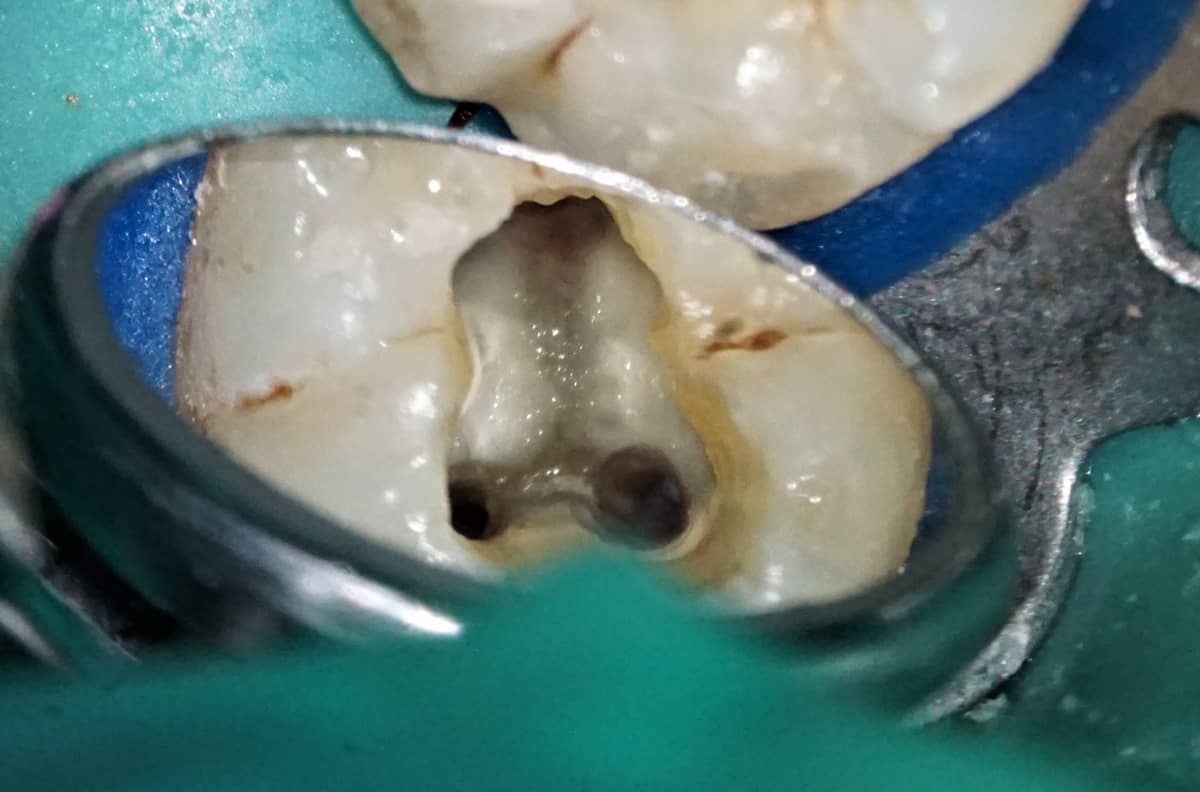

A gyökérkezelés célja, és lényege, hogy a fogat ellátó ereket és idegeket a lehető legtökéletesebben eltávolítsuk a fog gyökércsatorna-rendszeréből. Ehhez hagyományosan sajnos elég sok ép foganyagot el kell vennünk, hogy rendesen hozzáférjünk a csatornák kezdetéhez, illetve az úgynevezett pulpakamrához, amely a fog koronai részének belsejét jelenti. Ilyenkor gyakorlatilag ennek a kamrának a tetejét kell eltávolítani: itt „lakik” a fogbél.

Hosszú távon azonban a tető eltávolítása a fog töréséhez, adott esetben korai elvesztéséhez vezethet (fenti kép).

A mikroszkópos gyökérkezelési technikával azonban új, korszerűbb lehetőségek is rendelkezésünkre állnak. A hagyományos beavatkozáshoz képest ezt minimál invazív eljárásnak nevezzük, utalva arra az igen fontos tényre, hogy a lehető legkevesebb foganyagot távolítjuk el az egyébként is sérült fogból – hiszen gyökérkezelést rendszerint olyan fogaknál alkalmazunk, amelyekből már hiányzik több-kevesebb anyag. Ilyen esetekben pont a fentebb említett kamratetőt nem fúrjuk el, ami a fog hosszú távú megtartását segíti elő.

Az úgynevezett Truss technikánál kizárólag a csatornák felett fúrunk, így például az alsó, 2 nagy gyökérrel rendelkező rágófogak esetében a képeken nyíllal jelölt, jelentős mennyiségű foganyag megőrizhető.